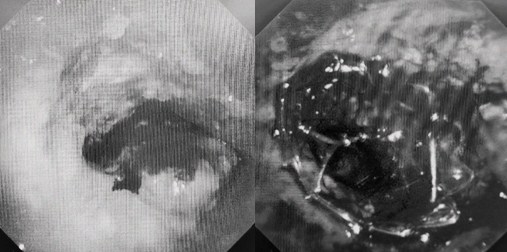

患者入院第二天,在麻醉手術(shù)中心全力配合下,歐陽(yáng)海峰帶領(lǐng)呼吸介入團(tuán)隊(duì),歷時(shí)40分鐘快速置入硬質(zhì)支氣管鏡、鏟切腫瘤,并順利植入全覆膜TTS支氣管金屬支架。患者氣短癥狀即刻緩解,為患者贏得了寶貴的后續(xù)治療機(jī)會(huì)。